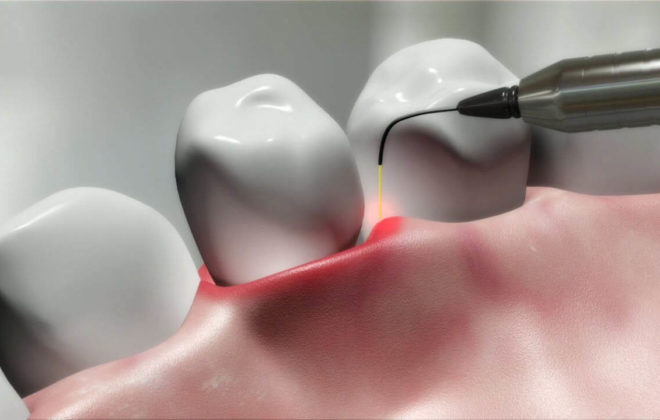

È considerato a ragione una delle più importanti scoperte del XX secolo. Il laser odontoiatrico è uno strumento medico che genera un raggio molto preciso di luce concentrata. Il raggio sterilizza la zona-bersaglio e allo stesso tempo coagula i vasi sanguigni riducendo di conseguenza il rischio di infezione e il sanguinamento. Risultato: le sedute dal dentista diventano molto più brevi e rilassanti, e nella maggior parte dei casi non vi è neppure bisogno di ricorrere all’anestesia. Alcune procedure possono essere eseguite in una frazione del tempo richiesto dallo stesso intervento senza laser, con evidenti benefici sulla durata del cosiddetto “tempo-sulla-poltrona”.

L’efficienza del laser è basata sui tassi di picco di assorbimento dei materiali contenuti nei tessuti-bersaglio (duri o molli) e di altro materiale dentale (per esempio, emoglobina, acqua, idrossiapatite, e così via) di lunghezze d’onda uniche. L’energia ottimale viene fornita con la minima emissione possibile, basata sulle caratteristiche di assorbimento uniche e precise delle singole lunghezze d’onda. Alcune di queste lunghezze hanno un’affinità con l’acqua e con le strutture pigmentate in rosso, ciò che le rende particolarmente efficaci per le procedure sui tessuti molli della cavità orale.

L’applicazione pratica: l’interazione con i tessuti nella cavità orale. Quattro sono le possibili interazioni quando il laser entra in contatto con il tessuto dentale: la riflessione, l’assorbimento, la trasmissione e la dispersione (scatter). La riflessione ha luogo quando la luce laser si riflette sul tessuto dentale; con l’assorbimento, l’energia laser viene assorbita iniziando il trattamento (vaporizzazione, ablazione, coagulazione, ecc.).